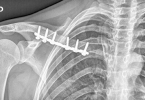

• 骨质疏松很严重怎么能快速补钙

骨质疏松很严重怎么能快速补钙

骨质疏松严重时需通过药物联合生活方式干预快速补钙,主要方法包括钙剂补充、维生素D协同、抗骨吸收药物、饮食调整及负重运动。1、钙剂补充:碳酸钙、枸橼酸钙等钙制剂是快速提升血钙浓度的直接方式。碳酸钙含钙量高 ...